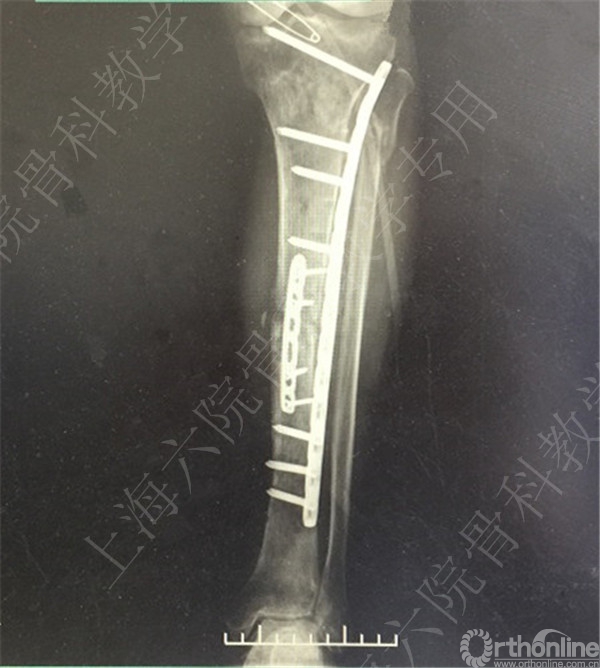

术后X线摄片示:骨折对位对线欠佳,稍成角。

患者复查,X线摄片示:骨折对位对线差,左胫骨立线欠佳,成角。